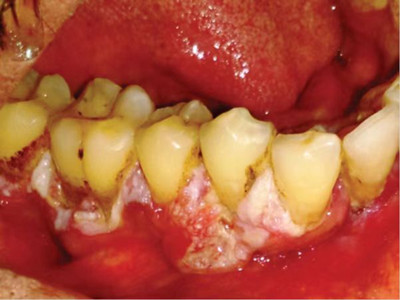

牙龈癌多源于牙间乳头及龈缘区,溃疡呈表浅、淡红,以后可出现增生。由于黏骨膜与牙槽突附着甚紧,较易早期侵犯牙槽突骨膜及骨质,进而出现牙松动,并可发生脱落。X线片可出现恶性肿瘤的破坏特征虫蚀状不规则吸收。

牙龈癌常发生继发感染,肿瘤伴以坏死组织,触之易出血。体积过大时可出现面部肿胀,浸润皮肤。